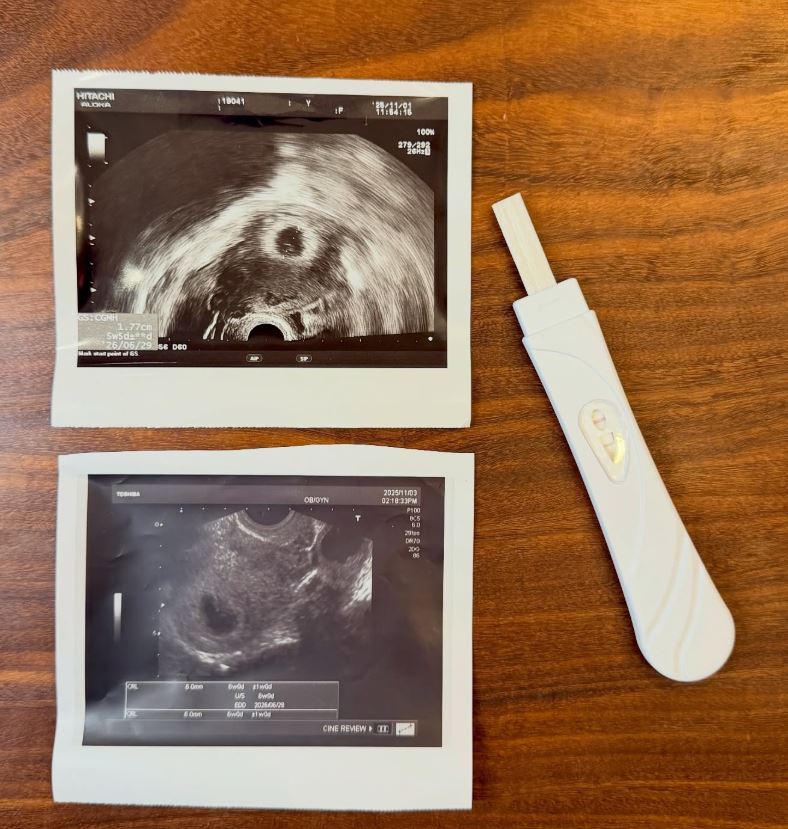

金老佛爺透露,2025年10月底,身體感到不太舒服,後來意外得知懷孕,為此還跑2間診所確認,她說:「醫生說好好養胎,等兩週後,第8週就可以領孕婦手冊了,其實,我已經有兩個孩子,但當第三次懷孕真的發生時,過去的經驗彷彿全部消失,腦袋一片空白」。

然而11月中檢查時,醫生說「看不到胎兒的心跳」,她當場崩潰大哭,醫生解釋,通常8~9週,不健全的胎兒會自然被淘汰,她後來並未做手術,「12月底肚子突然劇痛,無法入眠,我在床上翻來覆去,身體出現異常感覺,我跑去洗手間,羊水破了,接下來的過程,和生孩子一模一樣。」